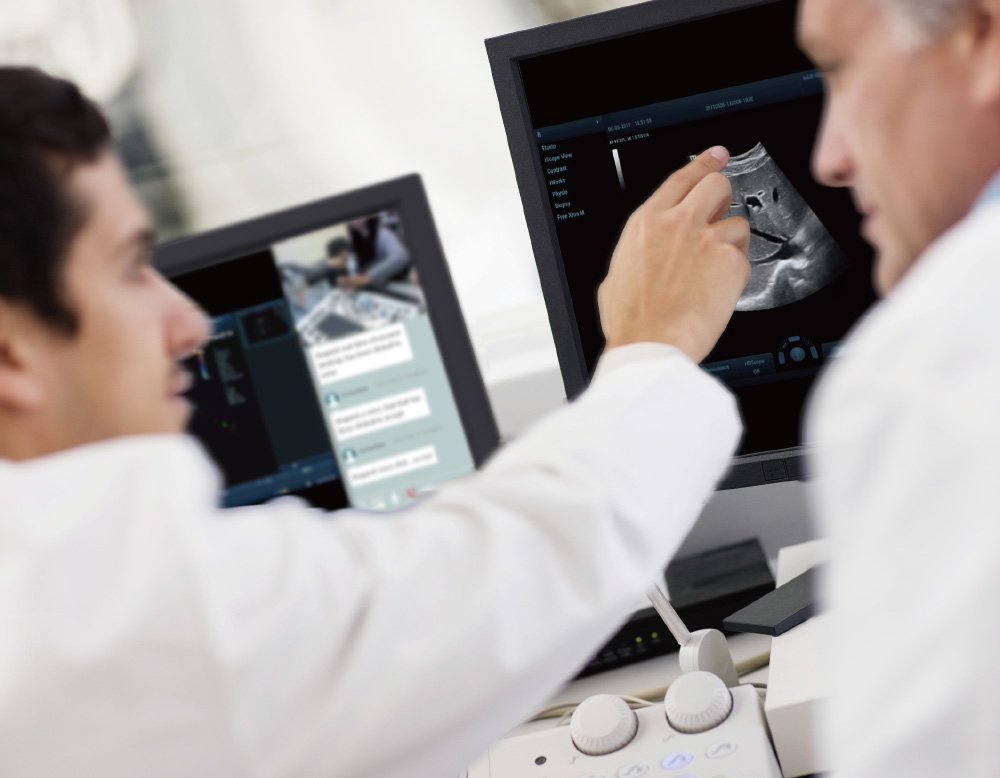

Integreert MiCo+ met de TE Air App om realtime delen van echografie?n, inclusief beelden, audio en video, naar het eindapparaat mogelijk te maken, voor begeleiding, training, kwaliteitscontrole, casusbesprekingen en meer